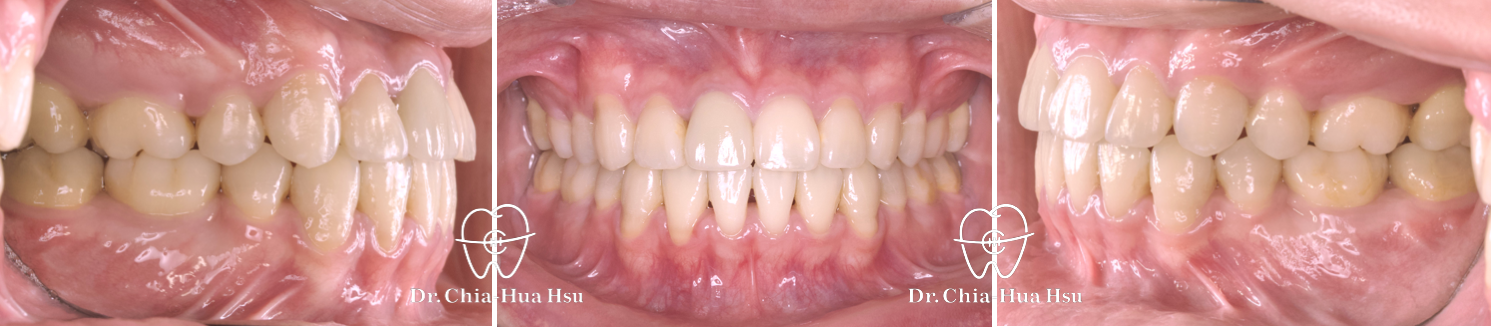

前牙錯咬、齒列擁擠

成人矯正 | ⾦屬矯正 | 拔牙治療

• 病患主訴:牙齒凌亂擁擠、笑起來不好看。

• 問題分析:患者是標準的骨骼一類咬合(Skeletal Class I)伴隨齒列擁擠以及前牙錯咬。

• 治療方式:拔除四顆小臼齒,使用傳統金屬矯正器將牙齒排列整齊、咬合緊閉。

• 治療時間:1 年 10 個月。

• 治療結果:齒列排齊,笑容更燦爛。

治療前

治療後